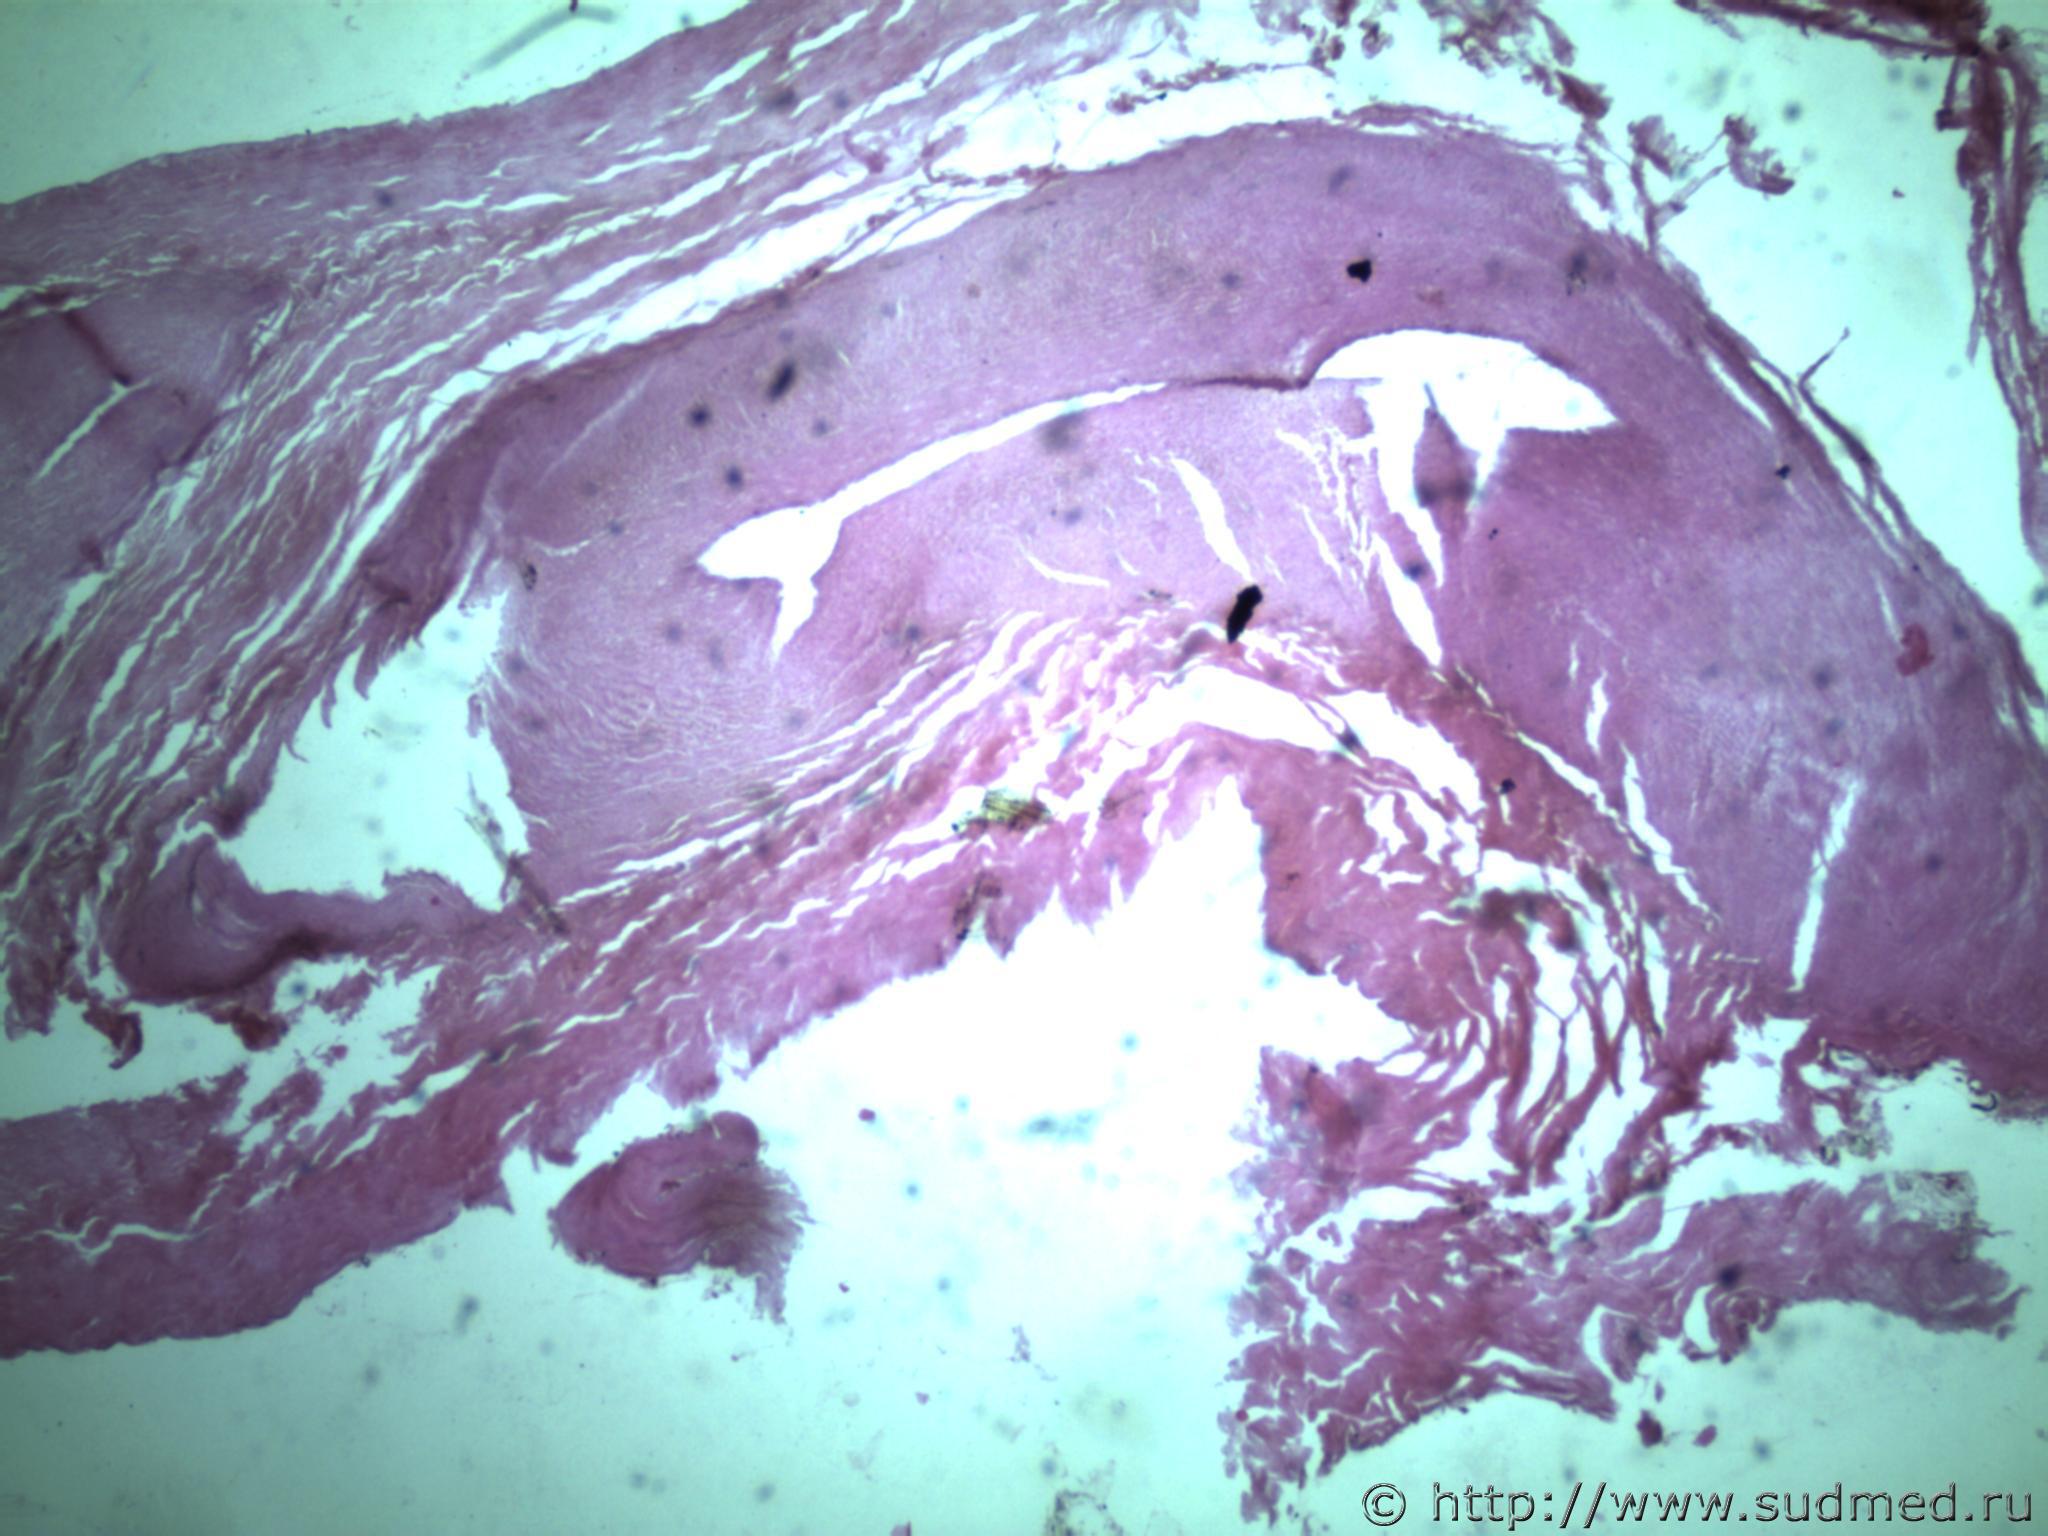

всем здравствуйте. хотела бы знать ваши мнения. провожу экспертизу. препараты как и труп новорожденного гнилые либо в аутолизе страшном. в легком картина такова, что ткань "плотная". просвет различимых альвеол в виде щелей и по всем полям зрения элементы околоплодных вод. одна артерия пуповины спазмирована. остальные сосуды непонятно : просвет их спавшийся но без признаков спазма. они как будто сплющены. да и сама пуповина в виде тонкого тяжа, видно из-за гнилостных изменений. под тмо спинного мозга признаки кровоизлияния, как и в коже с шеи. в коже головы с полнокровием отдельных сосудов. мать утверждает что ребенок после родов не сразу но все же шевелился и кричал. хотя перед этим он выпал у нее из матки на пол, ударившись головой. и со слов матери у него была пена изо рта и он хрипел.

Судебная медицина - Прикрепленное изображение Судебная медицина - Прикрепленное изображениеСудебная медицина - Прикрепленное изображениеСудебная медицина - Прикрепленное изображениеСудебная медицина - Прикрепленное изображение

ну вот как то так. там еще и фотки пуповины.

Плохо,материал гнилой.

Остановился бы на дышавшем лёгком.

5 фото в сообщении №4 и 8 фото в сообщении №5 не наводит ли на мысль о дышавшем лёгком ?

Про остальные фото молчу,там или ничего не видно или же есть оптически пустые пузыри,что вероятнее всего,проявления гниения.